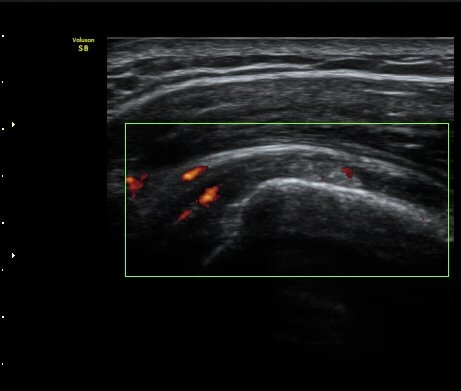

±Ø»ó°Ç Á¾´Ü¸é°Ë»ç¿¡¼­ Á¤¸Æ³¶³» ¼ö¾×Àú·ù¿Í ±Ø»ó°Ç³» ¼®È¸È­À½¿µÀÌ °üÂûµÈ´Ù(±×¸² 2, 3).